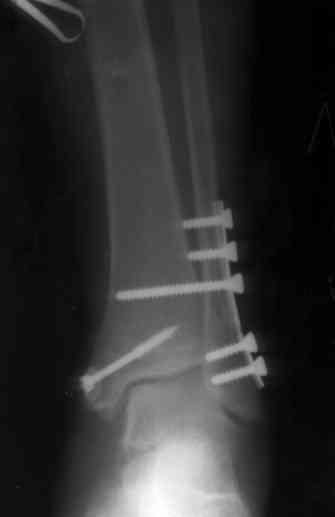

После проведенной дискуссии пришел к выводу, что трансартикулярная диафиксация не совсем приемлима с учетом современных методик остеосинтеза. Кроме того, вычитал, что хрящ разрушается на расстоянии до 0,5 см от места проведения спицы.

Пока я был в интернатуре, предпочитали осуществлять стабильный остеосинтез с ранней функцией. См. приложения и полнотекстный вариант

статьи.